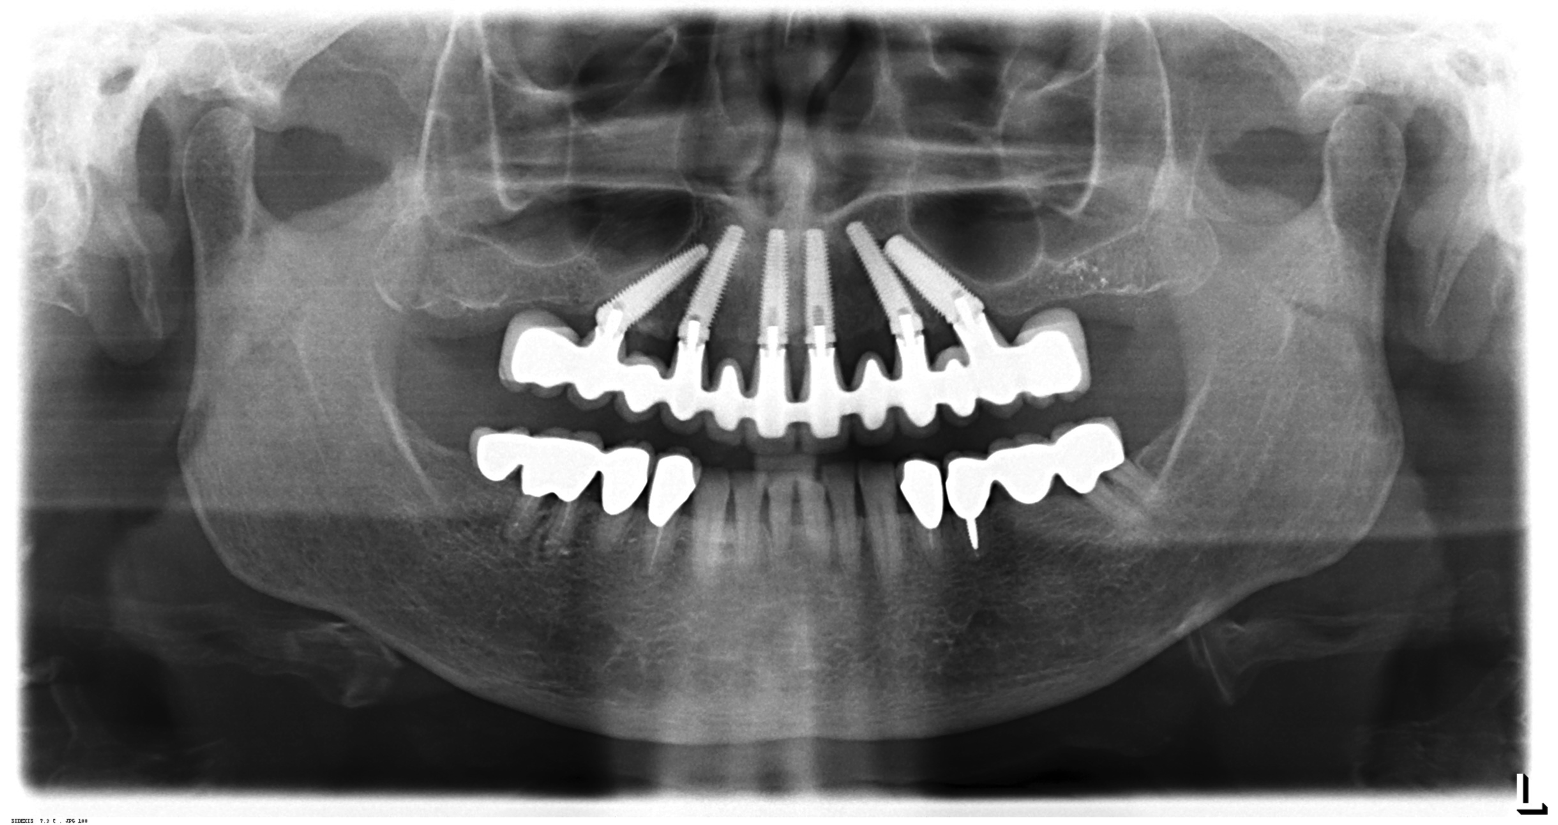

Fig 11. Panorex of clinical application of dual-axis principles. From left to right: 36-degree tooth No. 4; 24-degree tooth No. 6; 12-degree tooth No. 8; 12-degree tooth No. 9; 24-degree tooth No. 11; and 36-degree tooth No. 13. Angulation is designed to avoid maxillary sinus and buccal constraints of the anterior maxilla. (Image courtesy of Costa Nicolopoulos, BDS, Dubai, United Arab Emirates)

Figure 11

With the increased application of this concept, more options have been introduced, including 24-degree and 36-degree correction (Figure 11 through Figure 13). At present, larger angular corrections are available with external hexagon connection systems, while the 12-degree connection is also available in most internal connection configurations.

The author has used the dual-axial implant fixture unconventionally in the anterior mandible in an orientation that avoids perforation into the floor of the mouth (Figure 8).5 Dual-axial implants have also been used to avoid critical anatomic structures, such as the maxillary sinuses (Figure 9) and inferior alveolar nerves (Figure 10),47 thereby reducing the need for grafting procedures. Because these implants have subcrestal angular correction, they can be used with standard uniaxial abutments in a common path of insertion, thus enabling screw retention.